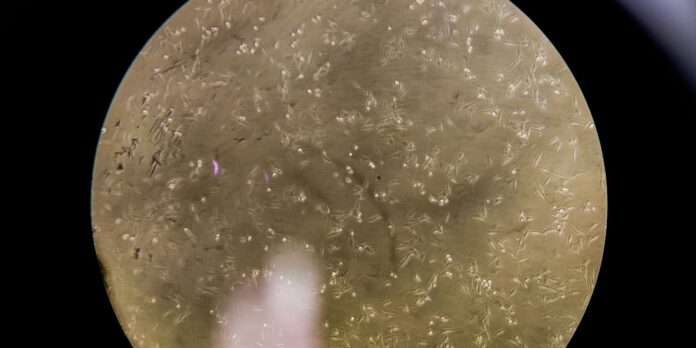

O estudo feito em camundongos adultos demonstrou pela primeira vez que o vírus invade o hipotálamo, desencadeando uma resposta inflamatória que prejudica a sinalização da insulina e altera o equilíbrio da glicose.